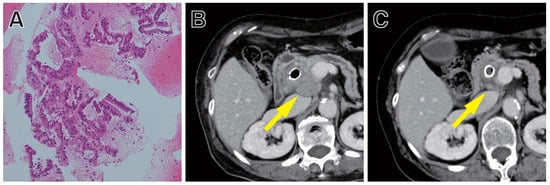

ICIs have emerged as a new treatment paradigm for patients with many types of cancer [124,125]. Immune checkpoints are a normal component of the immune system that inhibit the immune response to protect the host from excessive immune responses, in order to maintain immune homeostasis. However, some cancer cells utilize this immune checkpoint mechanism to attenuate the immune response and survive [126]. ICIs bind to immune checkpoint proteins or their ligands and block these immunosuppressive signals. Although, until now, only a limited number of cancer patients have been shown to derive benefit from ICIs, MSI-high (MSI-H)/mismatch repair-deficiency (dMMR) is considered a biomarker for predicting the efficacy of ICIs [127,128] (Figure 2).

Members of the tropomyosin receptor kinase (TRK) receptor family, encoded by NTRK1, NTRK2, or NTRK3, are expressed in nervous tissue and are known to play roles in the development of the nervous systems and in pain perception [164]. Fusions involving these NTRK genes result in a TRK fusion protein that stimulates cell proliferation through the constant activation of signal transduction in cancer cells (Figure 3) [165]. These fusions are found at high frequencies in rare cancer types, such as secretory breast carcinoma [166] and mammary analogue secretory carcinoma of the salivary gland [167]. On the other hand, the frequency of NTRK fusion was low, less than 1.0%, in PCs [165,168].